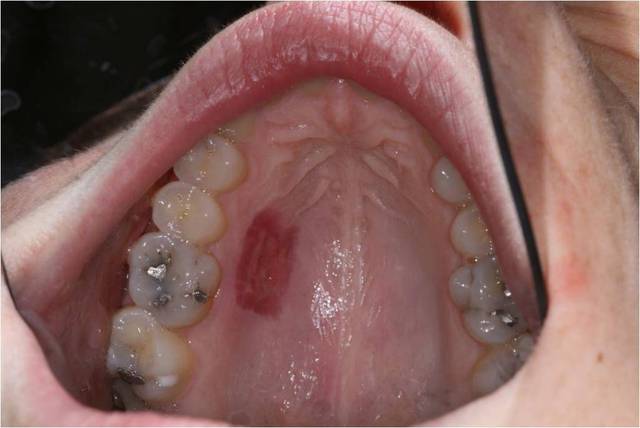

J'ai bientot ma premiere GEC solo . Voila le dessin de mon lambeau en demi epaisseur qu'en pensez vous ?

La 2ieme photos correspond au dessin final du lambeau